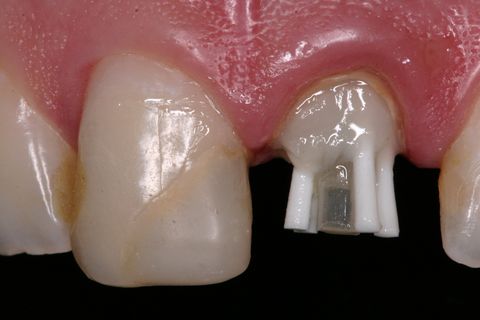

Preparo protético do núcleo

Para concluir a proposta restauradora, foi realizado o preparo protético do núcleo para a confecção futura de uma coroa total em cerâmica (Figura 25).